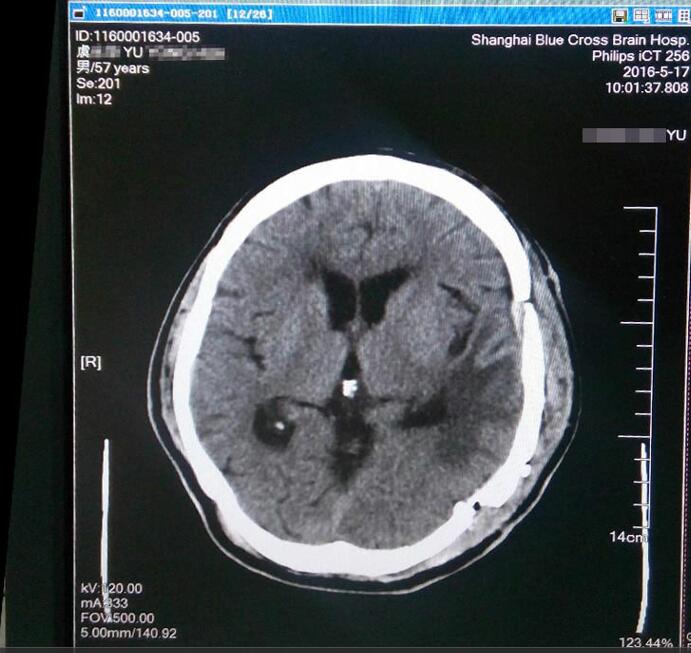

虞文軍這才意識到問題的嚴重性,至當?shù)蒯t(yī)院就診,行頭顱CT檢查示:左側(cè)顳區(qū)底部大腦凸面可見類圓形略高密度占位病變,周圍見低密度水腫影,CT值為44HU,大小約為8*6cm,周邊腦組織及腦室受壓,中線結(jié)構(gòu)右移,額頂部軟組織腫脹,考慮為左側(cè)底部腦膜瘤。為求進一步治療,經(jīng)過四處打聽,虞文軍在愛人的陪同下于2016年4月22日前來上海藍十字腦科醫(yī)院就診。

術(shù)前檢查腫瘤清晰可見

患者入院后行頭顱MR+增強及MRA發(fā)現(xiàn):腫瘤供血豐富,供血起源于小腦幕上動脈。經(jīng)包括沈建康教授在內(nèi)的專家會診后,考慮到患者腦腫瘤巨大(8*6cm)、腫瘤周邊血供豐富,手術(shù)指征明確,常規(guī)手術(shù)切除恐出血過多,增加手術(shù)風險,決定術(shù)前先為虞文軍行“超選擇性全腦血管造影術(shù)+腦膜瘤供血動脈栓塞術(shù)”,對腫瘤供血動脈進行栓塞,減少出血量,再全麻下行“左側(cè)顳底部巨大腦膜瘤切除術(shù)”。 沈建康教授表示:“ 我10年都沒見過這么大的腦腫瘤了”。 患者術(shù)后隨即恢復清醒,自我感覺頭腦較前更清醒,語音、語速恢復較好,不到半個月便已能正常行走,順利出院。